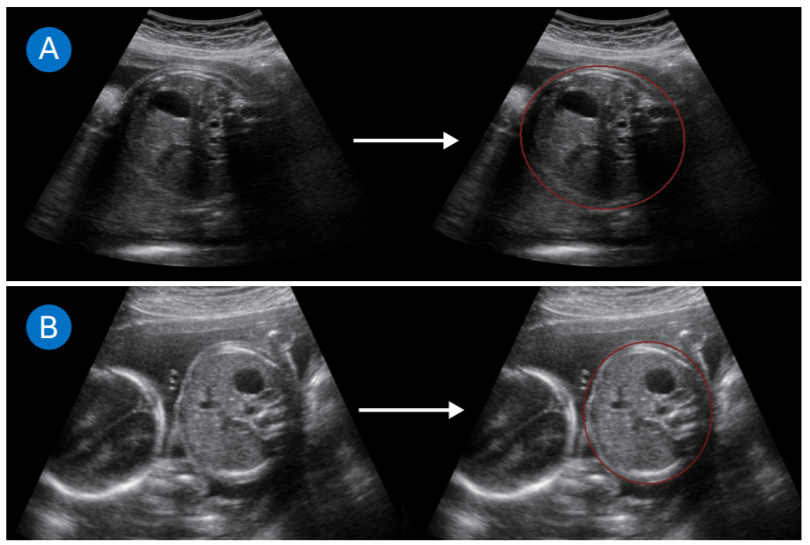

三星自动化超声测量以改善临床工作流程:通过OpenVINO™优化的胎儿和产妇检测。